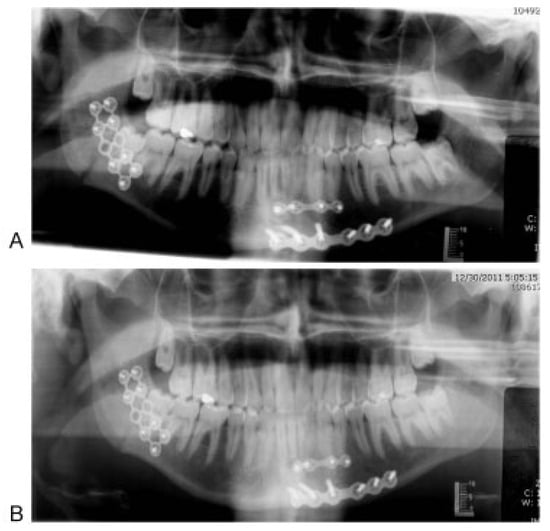

1.2. Surgical Technique

Strut Plate